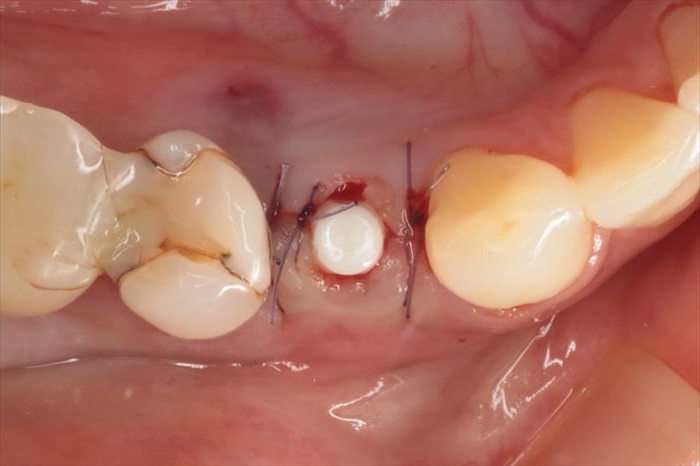

抜糸不要な吸収性縫合糸で垂直マットレス縫合しました。

埋入トルクは十分なことから6週後に仮歯を作成して噛めるようになります。

インプラントのネック部分をカバーするように粘膜を寄せて縫合しています。

仮歯作成時にはCO2レーザーを照射して余分な歯肉を蒸散します。